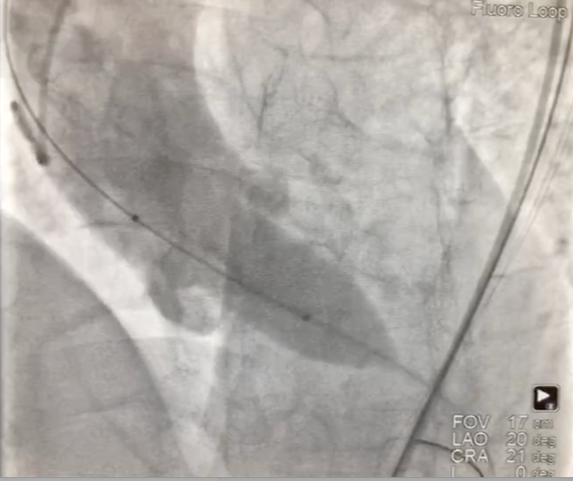

1、经右股动脉将Emboshield Nav6放栓塞装置输送至左、右颈内动脉。

2、经左股动脉入路,顺利跨瓣后,选取20 mm球囊于180 bpm下快速起搏预扩,显示无漏,左、右冠脉未受影响,但可见左冠窦、无冠窦巨大钙化团块。

3、按照既定策略,选择24 mm VitaFlow微创瓣膜,于180 bpm快速起搏下,快速一次性释放。

4、术后心电监护未见传导阻滞,心超提示人工主动脉瓣工作良好,瓣叶启闭正常,主动脉瓣峰值流速2 m/s,平均跨瓣压差6 mmHg,轻度瓣周漏。

主动脉根部造影示瓣膜位置合适(深度2 mm),轻度瓣周漏。遂释放瓣膜,撤回脑?;ぷ爸?,手术圆满成功。